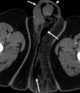

Fournier gangrene

Fournier gangrene is a type of necrotizing fasciitis or gangrene affecting the external genitalia or perineum. It commonly occurs in older men, but it can also occur in women and children. [Source: Wikipedia ]